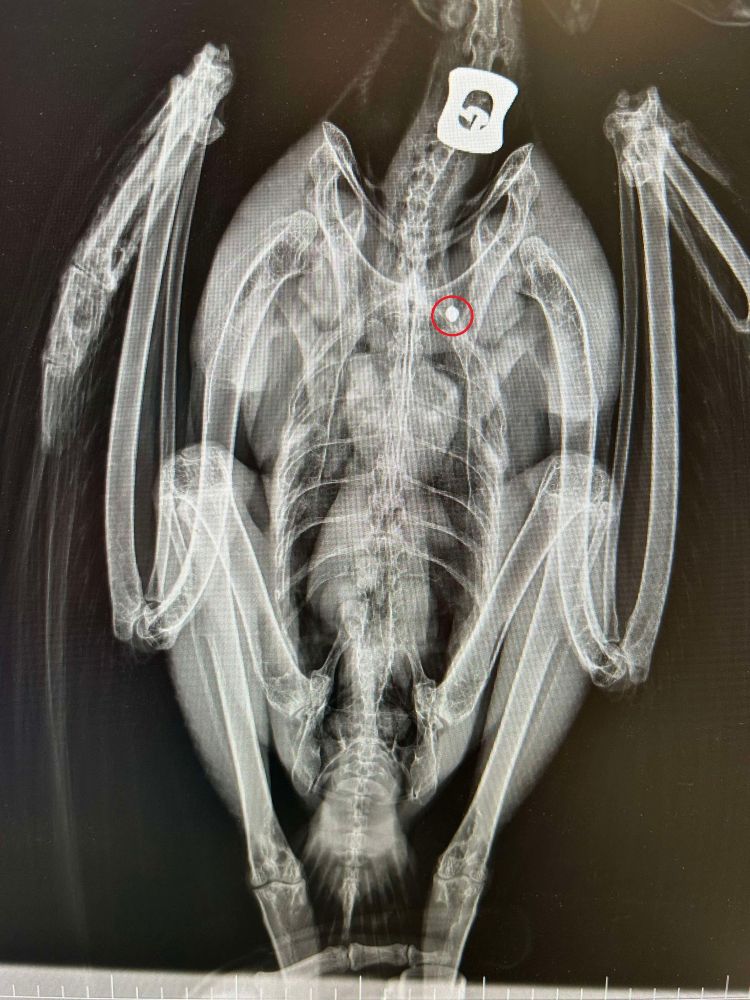

Lors de sa prise en charge dans notre clinique vétérinaire partenaire, une radiographie a révélé la présence d’un plomb logé dans sa cage thoracique, confirmant un tir de braconnage...